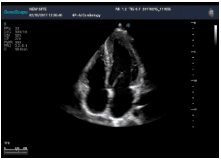

不同的探頭對應(yīng)于不同的臨床領(lǐng)域,不同的探頭頻率也應(yīng)用于不同的人體組織。超聲波在人體中的衰減與探頭頻率有關(guān),探頭頻率越高,穿透力越弱,分辨率越高,而探頭頻率越低,穿透力越強(qiáng),分辨率越低。因此在檢查淺表器官時應(yīng)選用高頻探頭,而檢查深部臟器時則選用穿透性強(qiáng)的低頻探頭。